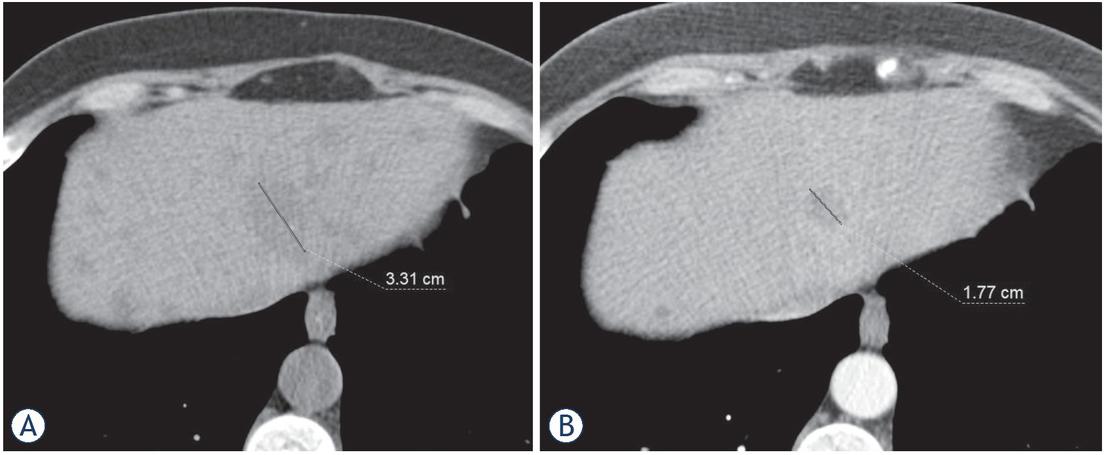

Figure 2